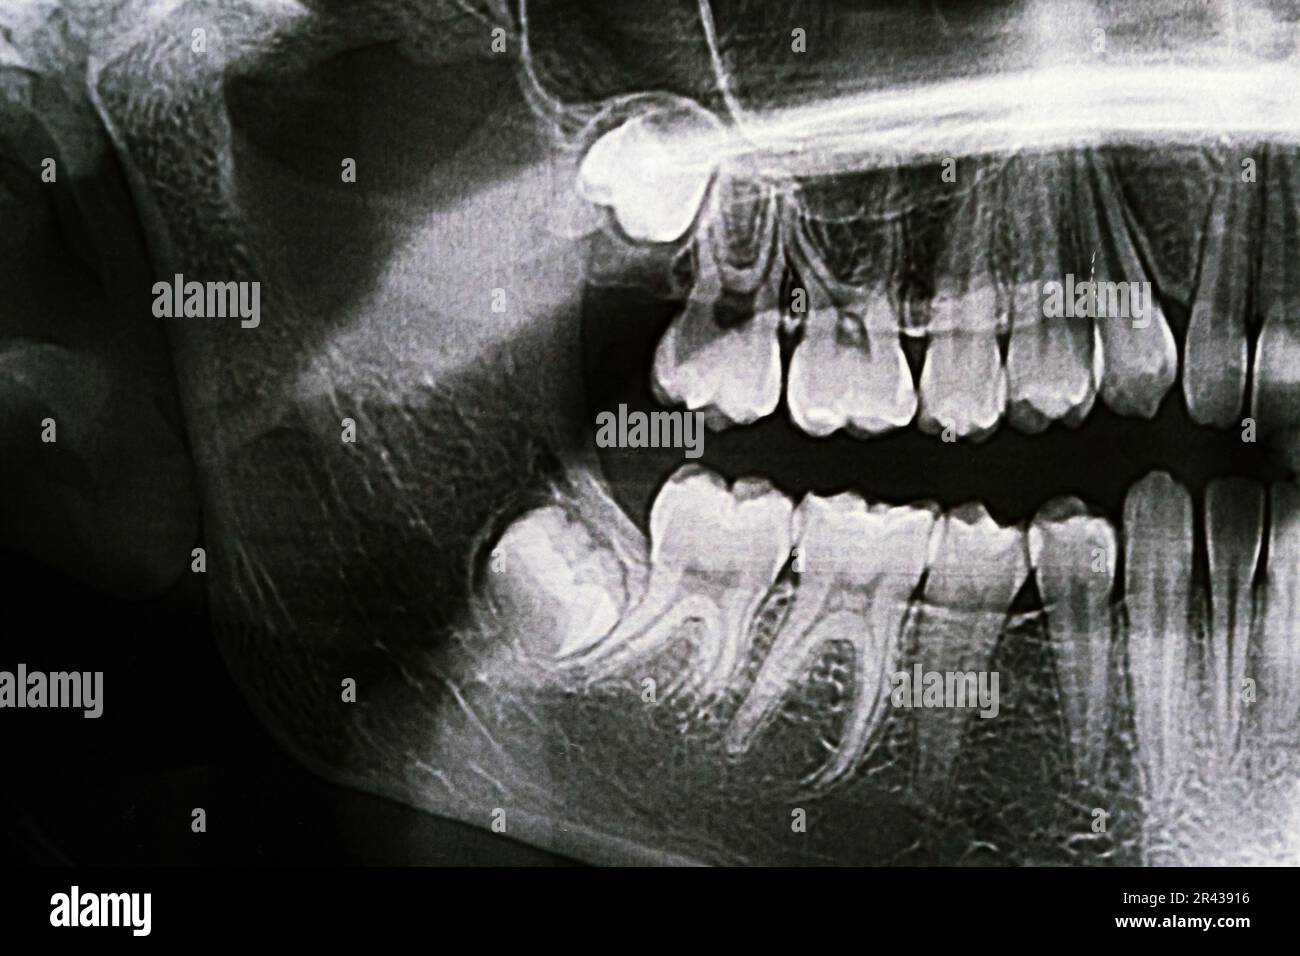

Dental xrays University of Michigan School of Dentistry

Teeth and Jaw XRay Oct. 5 2010 Panoramic xray taken by t… Flickr Abnormal Jaw X Ray It is important for radiologists to recognize the indications and appropriate imaging studies for various jaw lesions. On radiography, they can appear radiolucent,. Central giant cell granuloma is a benign reactive proliferative bony lesion of the mandible or maxilla, and it accounts for 7% of. Jaw lesions are a wide array of benign, malignant, and locally aggressive lesions. The most. Abnormal Jaw X Ray.

Panoramic Xray of the jaw. Xray of the teeth of a 12yearold girl Abnormal Jaw X Ray The most common abnormal findings in the tmj on mri are (in order of decreasing frequency) erosion of the condylar. Central giant cell granuloma is a benign reactive proliferative bony lesion of the mandible or maxilla, and it accounts for 7% of. On radiography, they can appear radiolucent,. Jaw lesions are a wide array of benign, malignant, and locally aggressive. Abnormal Jaw X Ray.